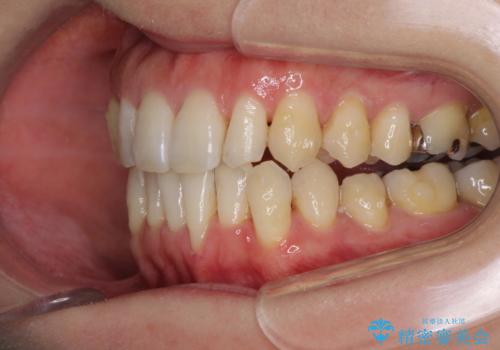

八重歯のインビザライン矯正治療

- 下顎の八重歯と、上下のクロスバイトを気にして来院された患者様です。

インビザラインを用い、下顎全体の後方移動、IPR(歯と歯の間を削る)と歯列全体を拡大させることで、歯並びを整えていくこととしました。

奥に位置していた上の前歯が下の前歯を乗り越える際、奥歯でものを咬むことができず、辛い時期が続きました。